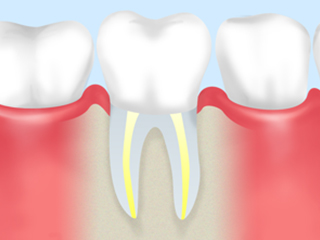

C3 虫歯の後期です。神経まで虫歯が進行しているので神経を取 る治療をし、歯の根の中を綺麗にしなければなりません。 今までの虫歯の状態に比べて治療の回数が増えます。 |

根管治療

歯の根の中は、中空になっていて、その中に神経や血管などが詰まっています。

虫歯などによって歯の神経に細菌が入り込んで炎症を起こすと、歯の神経は死んでしまいます。

深い虫歯などが原因で神経を取ったあと、根の中の中空部分をきれいにして処置をすることを根管治療と言います。

神経を取り除いたあとは、代わりにコアと呼ばれる土台を入れます。

神経がないので、痛みなどの危険を脳に知らせることが出来ません。

また、神経を取るということは血管なども一緒になくなってしまうので

歯に栄養がいきわたらず、歯自体も弱くなってしまいます。